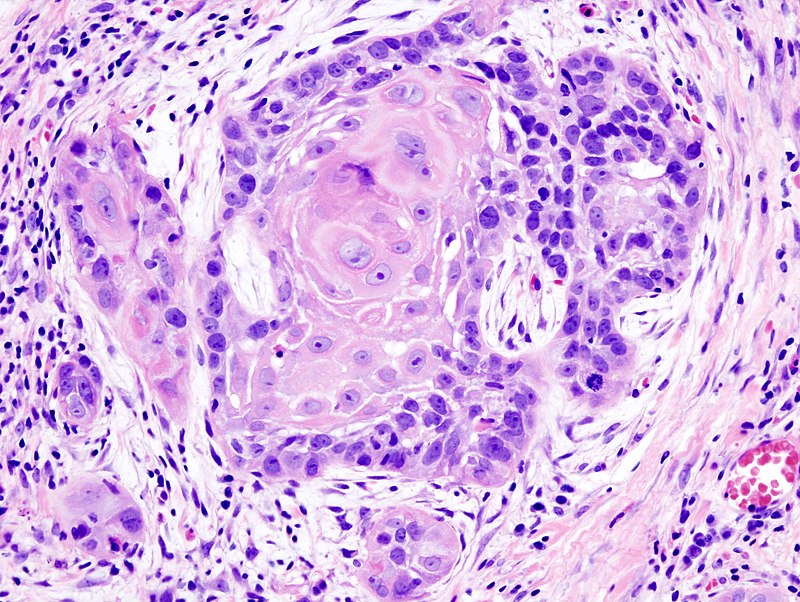

Squamous Cell Carcinoma

Squamous cell carcinoma (SCC) is the second most frequently diagnosed cancer worldwide.

Squamous cell carcinoma (SCC) accounts for about 30% of cancer cases in men and 20% of cases in women.

Two important risk factors for squamous cell carcinoma (SCC) are alcohol and tobacco use.

Invasive squamous cell carcinoma (SCC) may develop from oral leukoplakias and erythroplakias, which are precancerous diseases.

Although they can appear anywhere in the oral cavity epithelium, these lesions typically grow at the mouth’s floor.

Histologically, squamous cell carcinoma (SCC) is identified by alterations in the stratified squamous epithelial layers, such as invasion into the underlying connective tissue and hyperkeratosis, parakeratosis, acanthosis, keratin pearls, and dysplasia.